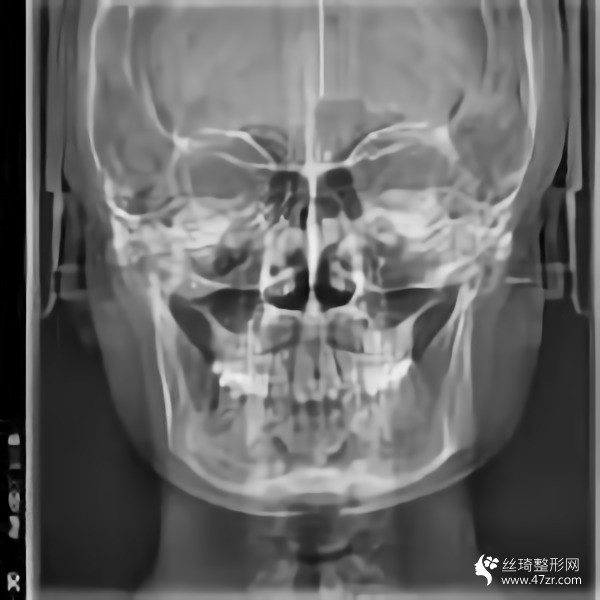

從高中開始,人們就一直說我的臉很方。就算不直接說臉,我也會說臉很大。每次聽到心里都很無奈,臉上都在埋怨我...每次我回嘴的時候,也是一副滿不在乎的表情。然而,我的心還是不自覺地開始關心它。說白了,我要小一點的臉。其實我一直有做下頜角的想法。之前我還在讀書,沒錢?,F(xiàn)在出來工作了,經(jīng)濟獨立了,咨詢了醫(yī)院說可以,終于可以解決這個大面子問題了

手術后15天。過來拆線。反正我覺得我更喜歡自己。一點都好看??雌饋砗芸蓯?。目前有點腫,但輪廓線條開始慢慢顯現(xiàn)。畢竟拆線?;謴蜖顟B(tài)還是很滿意的。目前較重要的是照顧好自己。父母不在身邊。我還沒有過恢復期。我不能吃得太隨便。我必須注意我的飲食。這個真的是先苦后甜。不過為了后面的恢復果,一切都是值得的

回來快一個月了,基本沒有腫脹,輪廓清晰柔和。不知道是不是錯覺,感覺皮膚細膩多了。哈哈,雖然有美顏加持,但是大家看不出來很正常,但是可以自己感受一下。院長的技術真的很好,不愧是變臉王。剛來的時候看到幾個美女好像是花錢磨骨頭的,表現(xiàn)的多火啊。合格的醫(yī)生就是不一樣,讓人安心。醫(yī)院里的人手術后一直在回來康復。說起來有點太熱情了,讓我不敢接電話。

我又來了。我不記得上次是多久了。年紀大了記憶力下降了很多,但身邊認識的很多人也會這樣。好像沒有明X的辦法。再說說我的下頜角手術。雖然手術的時候感覺不深,但是手術后確實記得很深,總是需要經(jīng)歷一些徹骨的寒冷,梅花才會有香味。較近的照片給你們發(fā)一波,如果手術做的好那么你以后就不會后悔了。

在生活中,我們往往忘記了健康和鍛煉,大多數(shù)人會在自己的世界里沉默,但生活中的許多實際問題仍然會把你拉回現(xiàn)實。我其實很喜歡去健身房,但是是時間問題導致我沒能得到我想要的。另外,我在下頜角休息了很久,臉部好了很多,運動還是不可或缺的。其實我覺得健康較重要,其次是外表和對自己的信任,哈哈